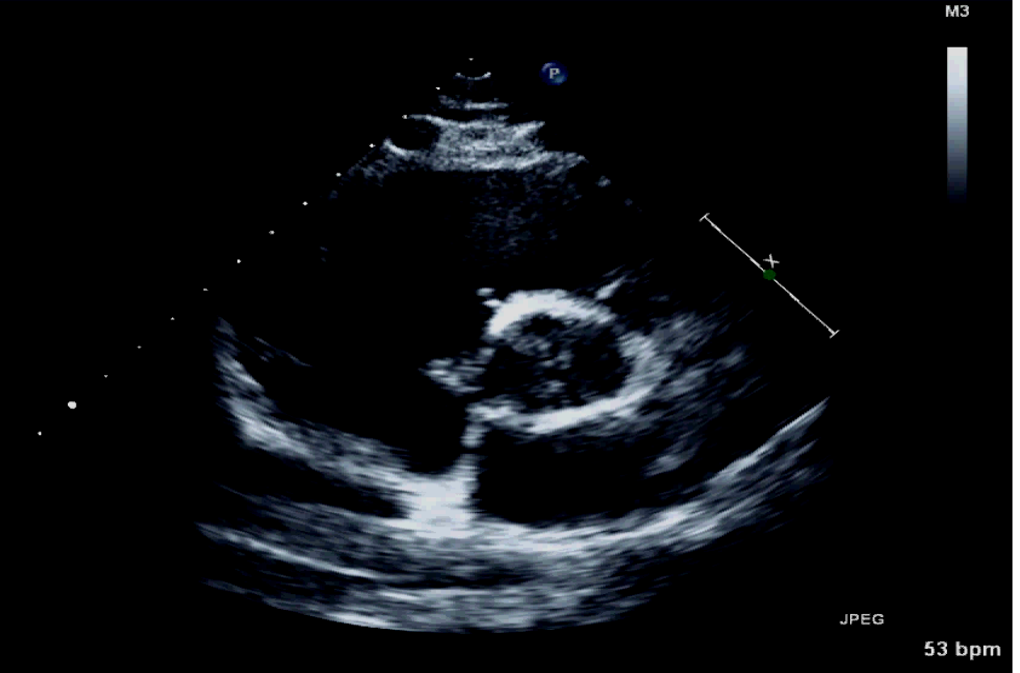

What is important for us to see for a PSAX base level? 3

A

Must see three things clearly

1. TV

2. AV

3. PV must be seen, but may not open up to PA

Where should we have the focus for the PSAX base image?

AV

Where should the depth be placed for a PSAX base image?

Slightly past LA